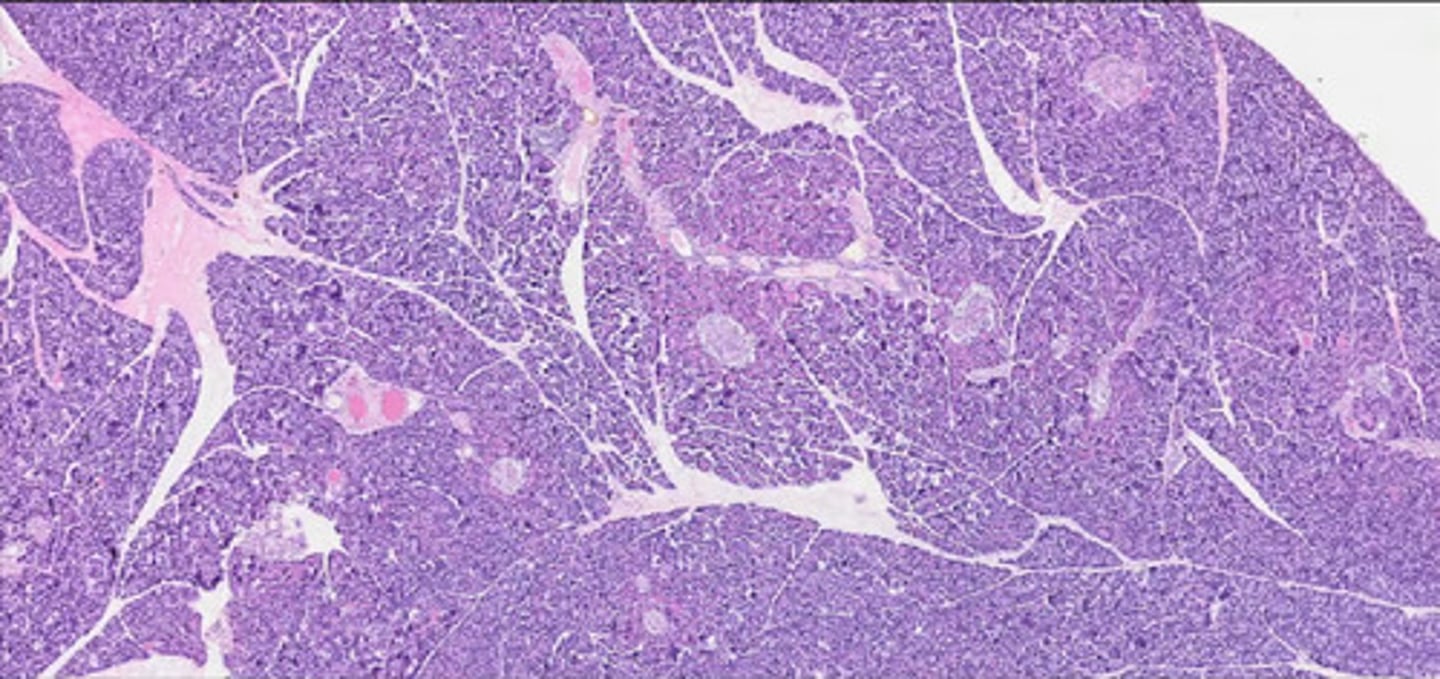

Grasica młodociana (H+E)

Grasica inwolucyjna (H+E)